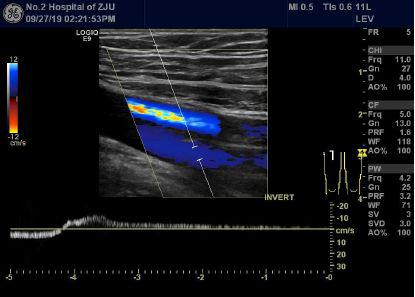

小徐B超图像:股静脉第一对瓣膜在屏气时可见返流信号,提示双侧下肢深静脉瓣膜功能不全